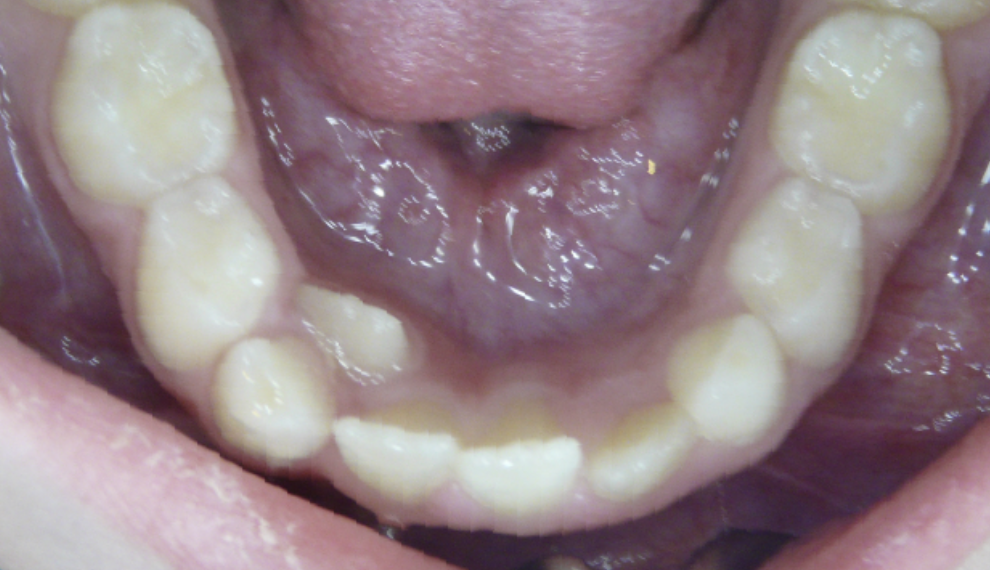

Crowding

Lack of space causes crowding as teeth erupt.